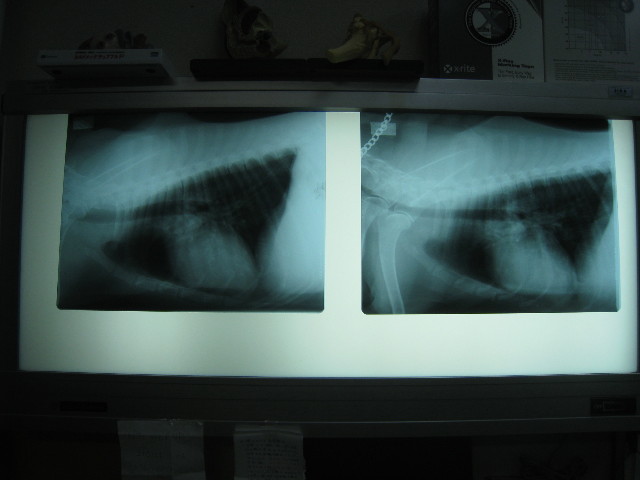

こちらは肺。

過去のフィラリアの影響などであいかわらず白っぽいけど、前回(7月2日)と変わっていないので大丈夫♪

左が7月2日。右が8月25日。